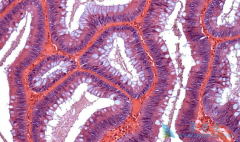

如今 西妥昔单抗 已从晚期转移性结直肠癌患者三线治疗药物跃升成为一线治疗药物。随着研究的深入,西妥昔单抗在ACRC患者的治疗中发挥者越来越重要的作用。三线治疗。证实西妥昔单抗三线治疗mCRC的临床研究有NCICCO.17,BOND等。NCICCO.17研究的主要目的 ...